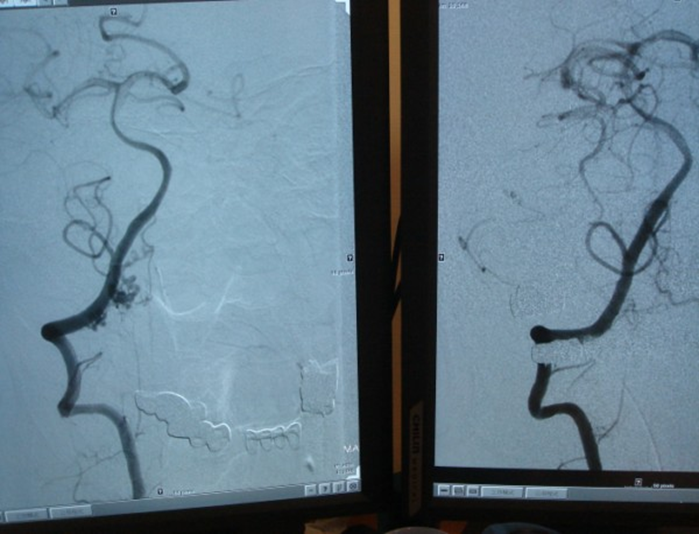

邱先生有頭痛病史,之前一痛廿幾天,神經內科為他腦波檢查並服藥,改善了一陣子,今年九月,頭痛又犯了,這次是讓他無法忍受的劇烈疼痛。七日凌晨兩點掛急診,當時值班的呂智勝醫師給了止痛藥卻未能見效,馬上替他做電腦斷層檢查,發現有顱內出血現象,立刻會診神經外科,經廖唯辰醫師確診為「自發性蜘蛛膜下腔出血」,影像醫學部接力做血管攝影,這是極為少見的案例。

栓塞手術是由嚴寶勝主任執行,羅中平醫師擔任助手。手術目的是把有問題的地方堵住,讓動靜脈血管各自回歸正常路徑,放射科醫師全副武裝包在重重的鉛衣隔離設備裡,導管從大腿股動脈進入,經心臟通到腦部,邊做邊照血管攝影,花上幾個小時尋找又細又彎,可能還很脆弱的畸形血管,有些血管看得到、做不到,拿捏栓塞的速度、劑量,都需要很高的技術,手術中血管破掉機率不低。廖唯辰醫師形容頸椎動靜脈血管畸形栓塞,是高難度手術,就像在腦幹旁邊拆炸彈。

影像醫學部團隊在如此困難的腦幹位置,找到邱先生兩條很細的畸型血管,成功栓塞,這類報告案例全世界也不多,在神經外科醫師眼中,臺中慈院執行血管內栓塞手術的技術已超越醫學中心,日本人報過六個案例,而嚴寶勝主任光是個人經驗就有二、三個,加上邱先生的案例,也可以提出世界級的論文。